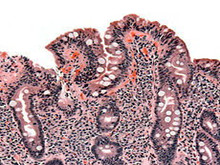

乳糜泻

乳糜泻以前被称为非热带脂肪腹泻,也被称为乳糜泻,是由麦胶引起的肠道疾病。本病主要...

血常规、粪便检测、活体组织病理检查(活检)